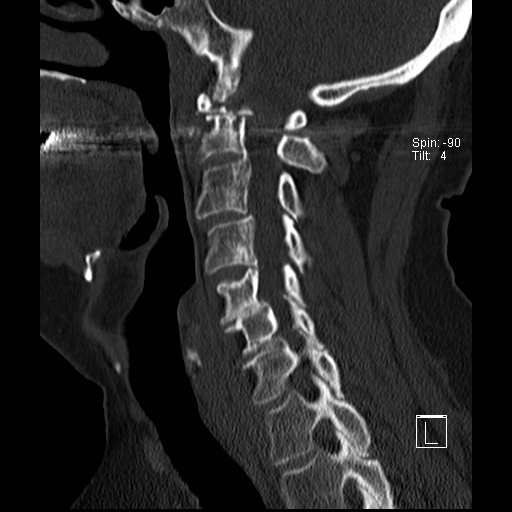

Lồng nền sọ

Lồng nền sọ, còn gọi là sụt lún sọ não hay ấn nền sọ, xảy ra ở 5-10% bệnh nhân viêm khớp dạng thấp cột sống cổ.

Trong lồng nền sọ, mỏm răng sa vào lỗ chẩm làm thu hẹp không gian dành cho tủy sống.

Biểu hiện lâm sàng đa dạng, từ đau đầu mạn tính, hạn chế vận động cổ đến suy giảm thần kinh cấp tính (chèn ép tủy sống và thân não, có thể dẫn đến liệt hoặc thậm chí tử vong nếu cổ bị di chuyển ở một số tư thế nhất định).

Hình ảnh

Cuộn xem các lát cắt CT.

Có hình ảnh di chuyển lên trên của mỏm răng vào lỗ chẩm.